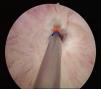

Caso 2. Varón de 9 años. Traumatismo pélvico y uretral (caída de bicicleta). Catéter de vesicostomía inicial permanente. Uretroplastia T-T a los 2 meses PO, con reestenosis. Segunda uretroplastia al año (injerto mucosa bucal) sin éxito (se reestenosa), presentando además orquitis repetición. Se decide uretrotomía endoscópica (fig. 1) a los 2,5 años del accidente, con nueva reestenosis. Posteriormente, 2 uretroplastias T-T (uretra bulbomembranosa), 4 y 5 años PO. A los 6 años del accidente, tras un año de la última uretroplastia, el paciente está asintomático y sin estenosis uretral.